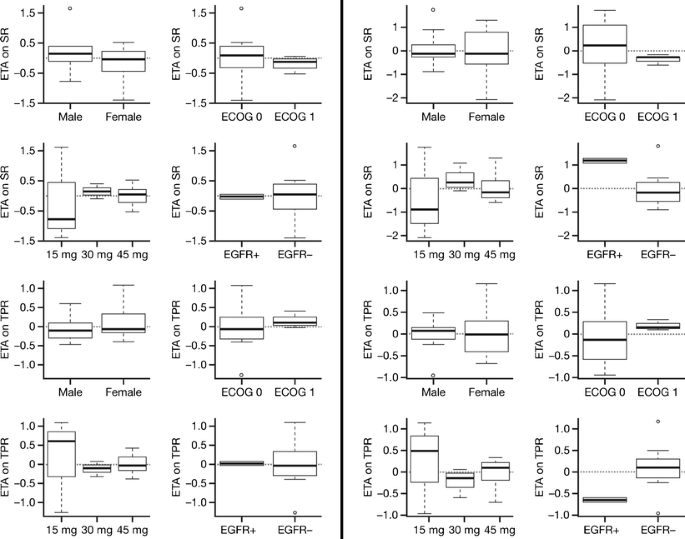

The model of tumor growth with the parameters for shrinkage and progression rates fitted the data for tumor size fairly well (Fig. 3). The observations versus population and individual predictions were uniformly and closely distributed around the line of identity. Table 5 lists the parameter and precision estimates. The covariate analysis identified that the shrinkage rate was significantly affected by EGFR mutation status. Figure 4 shows the individual model parameter estimates plots versus gender, ECOG status, dose level, and EGFR mutation status for the base model (without any covariates) and final model (EGFR on shrinkage rate). Shrinkage rate was 85% less in EGFR wild type versus EGFR mutant subjects. For the 15 mg cohort, although the variability around individual SR and TPR parameters was larger than for the other two dose groups, the available data did not support the addition of dose cohort as covariate, probably due to the small sample size evaluated in this study. No correlation with duration of treatment, progression-free survival, or overall survival was undertaken at this time.

Fig. 4

Individual variability in parameter estimates (ETA) for SR and TPR versus gender, ECOG status, dose group, and EGFR mutation status for the final model with EGFR on SR as covariate (left) and base model with no covariates added (right)